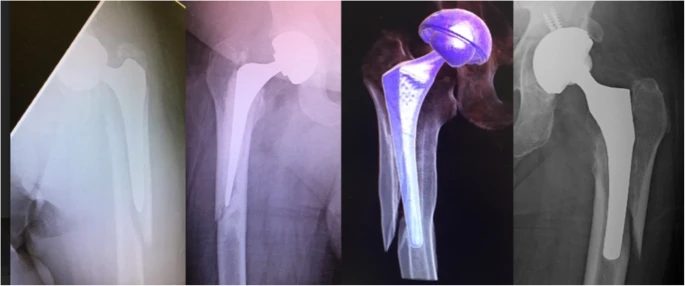

• Это название было выбрано по двум причинам: во-первых, оно является зеркальным отражением «переворота», а во-вторых, оно ведет себя как обратный косой перелом проксимального отдела бедренной кости с аналогичным супралатеральным смещением отводящей мышцы, подтягивающей проксимальный фрагмент.Подобные трещины произошли с зацементированными и несцементированными стволами (рис. 2).

• Хотя цель этого исследования не заключалась в изучении результатов лечения, в этом исследовании обратные переломы типа «flip-flop» обычно подвергались ревизии с эндопротезированием дистальной несущей ножки и фиксацией проксимальных фрагментов перелома серкляжными проволоками или пластинами.

• Показан пример пациента, которого лечили с помощью этого подхода, демонстрируя достижение заживления (рис. 3).

Режим обратного флип-брейка.

Рисунок 2. Схема обратного перелома с перевернутым верхом.

Артропластика и фиксация серкляжной проволокой при ретроградных переломах лоскута.

Рисунок 3. Артропластика и фиксация серкляжной проволокой при ретроградных переломах лоскута.